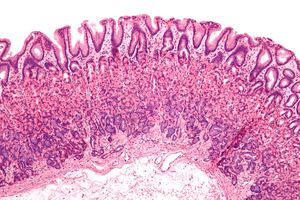

현미경 해부학은 현미경을 사용하여 육안으로 관찰할 수 없는 미세한 구조를 연구하는 분야이다. 조직학(조직 연구)과 배아학(미성숙 상태의 유기체 연구) 등이 현미경 해부학에 포함된다.[3]

육안으로는 관찰할 수 없는 미세한 구조에 대해 현미경을 사용하여 조사하고 구조를 기술하는 학문이다. 각 기관(장기) 내 구조의 특징을 구성하는 세포 수준까지, 또는 세포소기관 수준까지 밝힌다. 편의상 "조직학"이라는 이름으로 해부학과는 별개의 분야로 취급되는 경우가 많다.[1]4. 2. 3. 비교 해부학